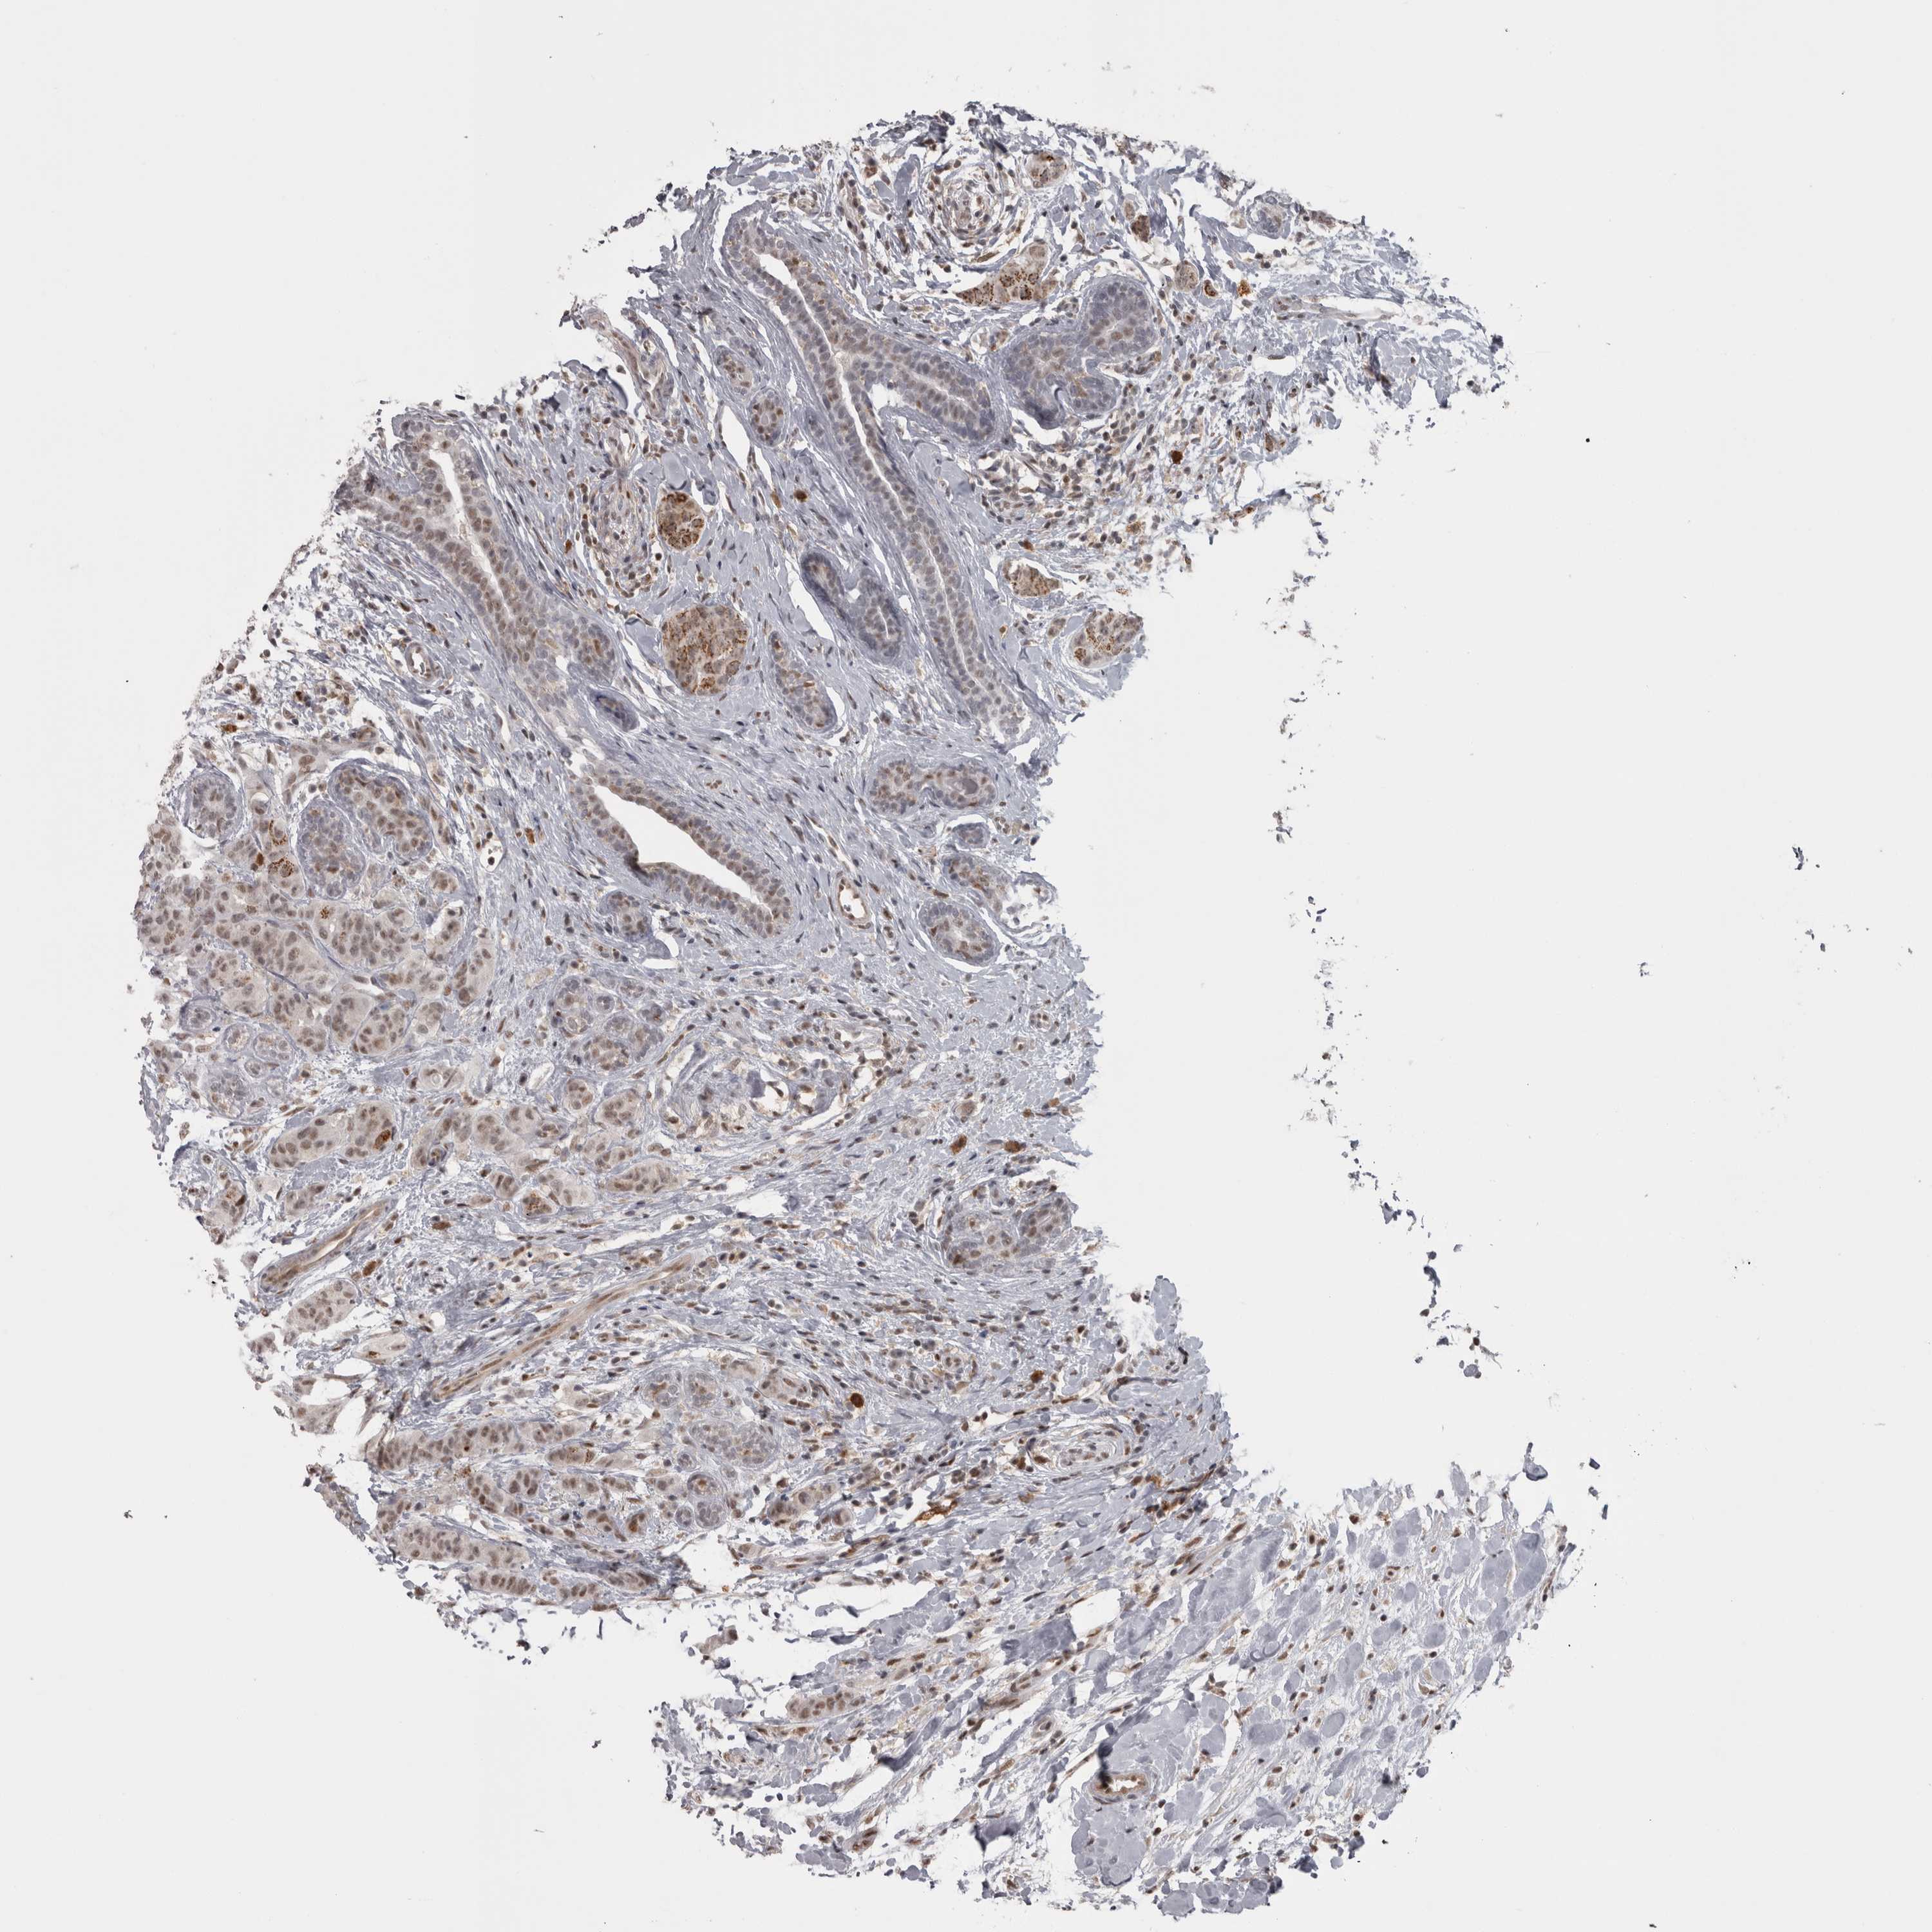

BRCA TCGA BRCA VALIDATION PROTEIN EXPRESSION

ANTIBODIES

AND

VALIDATION